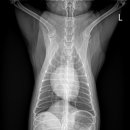

남양주 다산동물병원 24시 고양이건강검진 후기 신장검사 원동물의료센터 경기 남양주시 다산중앙로 15... 24시 동물병원에서 고양이 건강검진을 하고온 후기를 소개해드릴게요. ⏰ 영업시간: 24시 주차 ⭕ 병원...

이후에 병원에서 전화가 와서 아이를 데릴러 오면 되더라고요 특히 담당쌤이 검사결과를 보면서 건강상태와 주의 할점? 등등 자세히 설명해 주셨어요 남양주 다산동물병원 24시 고양이건강검진 베이직 검사...

중증, 만성질환 관리 시스템이 잘 구축되어 있어 장기적으로 꾸준히 관리받기 좋은 병원이라는 느낌을 받았어요. 남양주 다산동물병원 24시 고양이건강검진 원동물의료센터는 단순 검진을 넘어 아이의 삶...

안녕하세요 오늘은 성공적인였던 고양이건강검진을 다녀온후기를 올려봅니다. 저희 집 냥이님이... #남양주동물병원 #24시다산원동물의료센터 #남양주24시동물병원 #다산원동물병원 #다산고양이건강검진...

맛집후기!! 24시 다산 원동물의료센터 #남양주다산동물병원 #남양주다산동물병원24시고양이건강검진... 진행되는 남양주 다산동물병원 24시 고양이건강검진 전문 병원이에요! 여기가 카운터인데 깔끔하고...